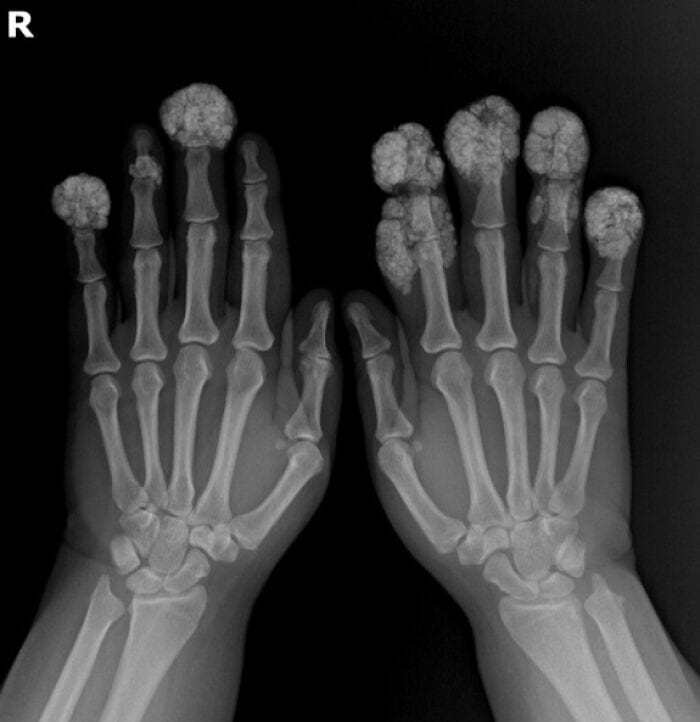

Проявления склеродермии кистей рук

Склеродермия кистей рук — это проявление системной склеродермии, хронического заболевания, характеризующегося уплотнением и фиброзом кожи, а также поражением кровеносных сосудов и внутренних органов.